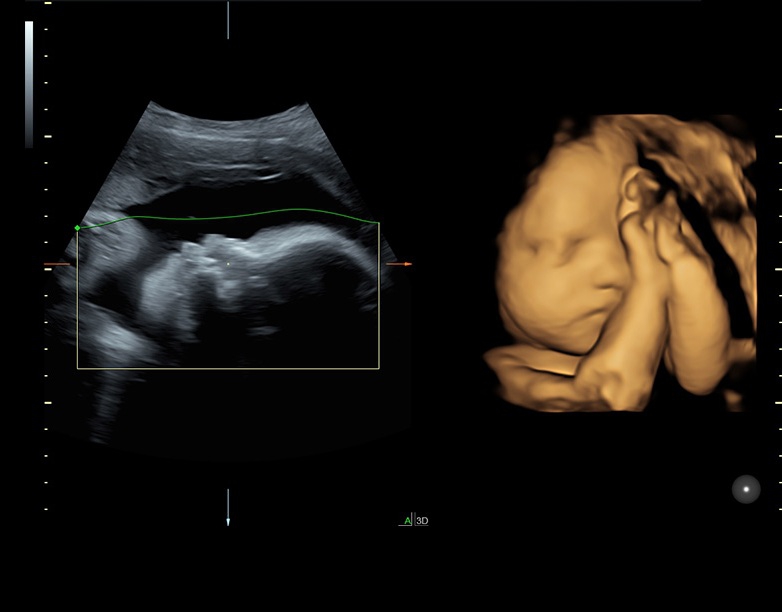

Ультразвуковая платформа Voluson S8 представляет собой оборудование экспертного класса с передовыми возможностями и высоким уровнем автоматизации процессов. Она позволяет проводить сканирование в режимах 2D, 3D и 4D с высоким качеством изображений.

• Технология SonoRenderlive: Эта технология облегчает получение 3D/4D изображений путем автоматического изменения положения плоскости визуализации в зависимости от движений плода. Она позволяет получить реалистичные и объемные изображения, что полезно для демонстрации плода будущим родителям и для дополнительного анализа.